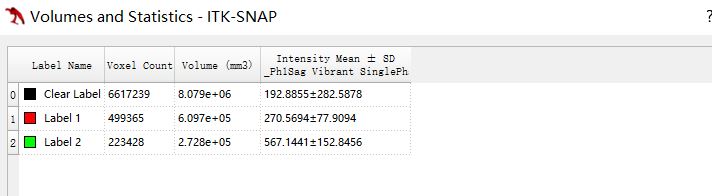

效果:

最后可以点击“Segmentation”菜单里面的“Volume and Statistics”查看定量结果。

本文详细介绍了如何使用ITK-Snap的自动分割功能,通过步骤3选择Clustering算法对乳腺动态增强序列进行分割,随后手动优化并设置种子点,最后展示测量结果。适合对医疗影像处理感兴趣的开发者和研究人员。

本文详细介绍了如何使用ITK-Snap的自动分割功能,通过步骤3选择Clustering算法对乳腺动态增强序列进行分割,随后手动优化并设置种子点,最后展示测量结果。适合对医疗影像处理感兴趣的开发者和研究人员。